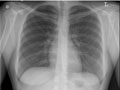

Normal:

The lungs look normal in size and shape, and the lung tissue looks normal. No growths or other masses can be seen within the lungs. The pleural spaces (the spaces surrounding the lungs) also look normal.

The heart looks normal in size and shape, and the heart tissue looks normal. The blood vessels leading to and from the heart also are normal in size, shape, and appearance.

The bones including the spine and ribs look normal.

The diaphragm looks normal in shape and location.

No abnormal collection of fluid or air is seen, and no foreign objects are seen.

All tubes, catheters, or other medical devices are in their correct positions in the chest.